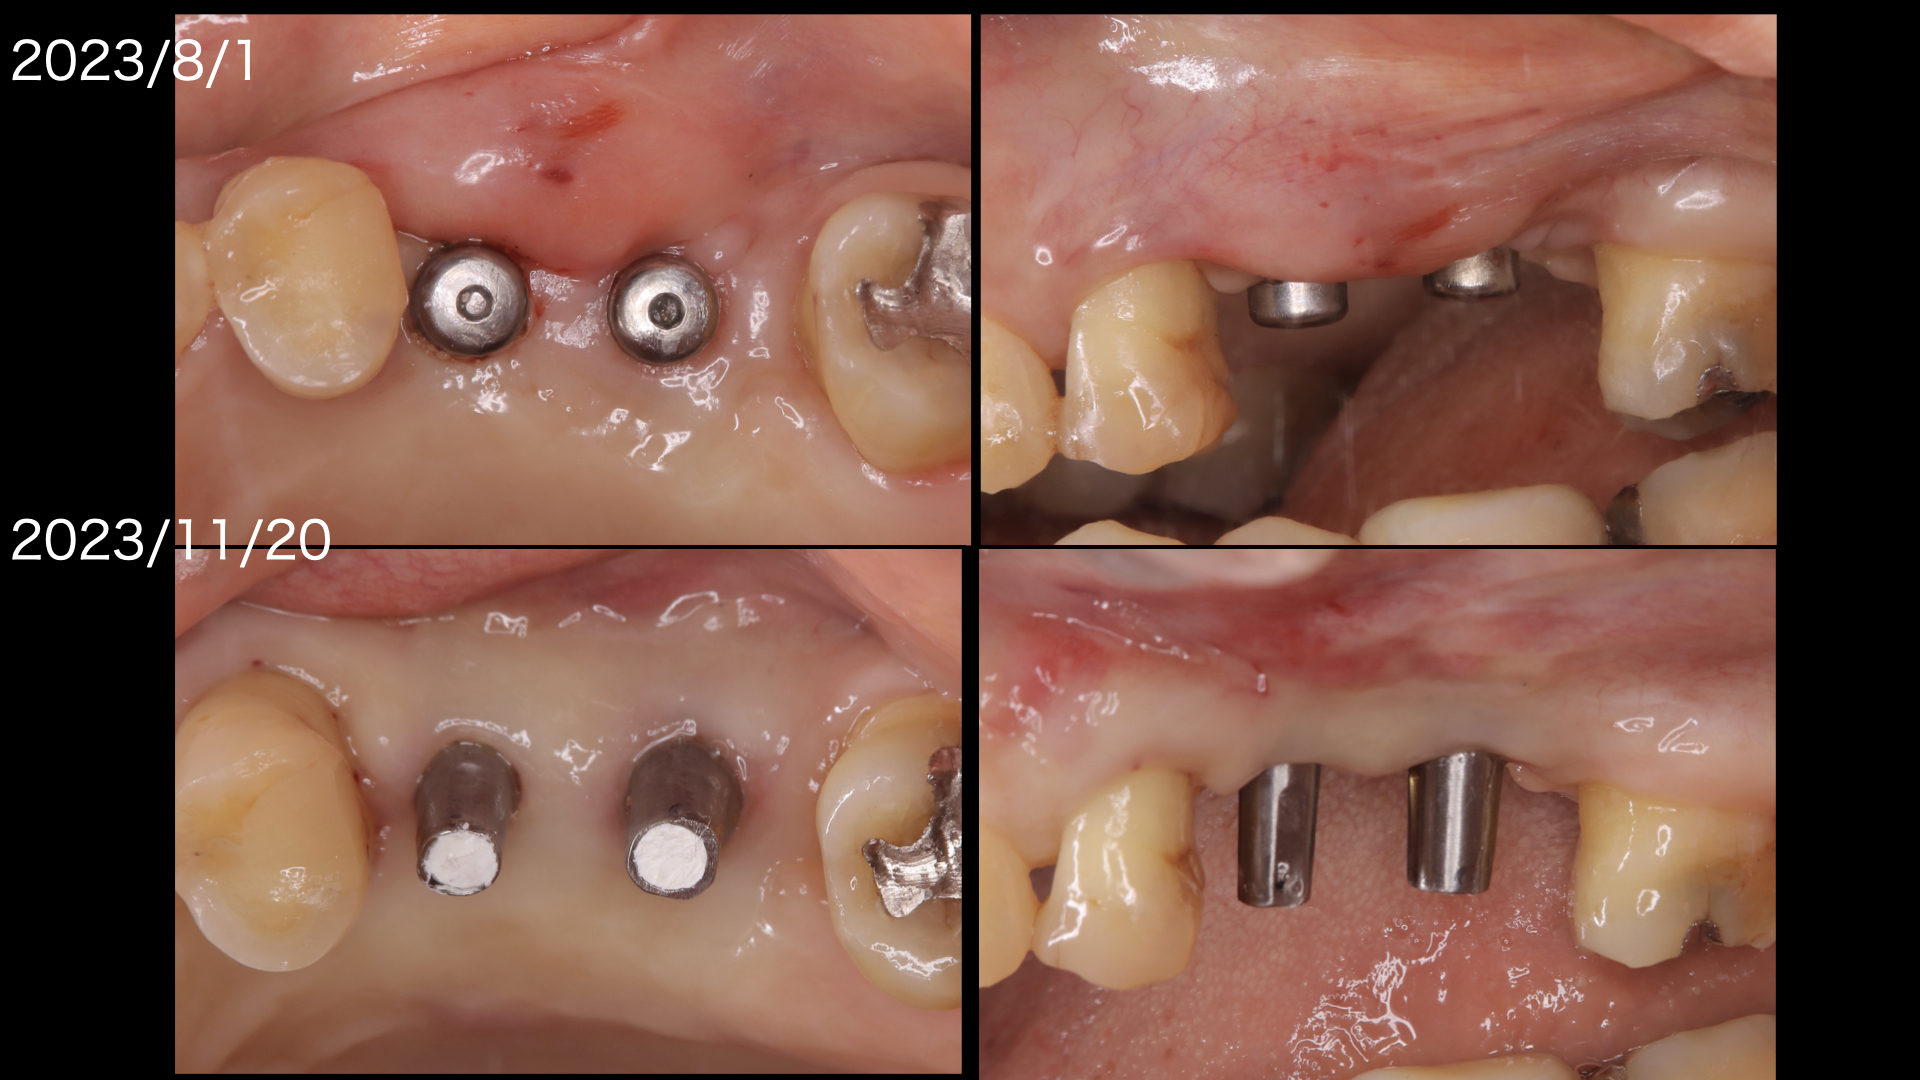

矯正が終わり、左上のインプラント治療に入ります。

もともと歯周病で骨が吸収していましたので、この部分にインプラントをおこなうには骨を造らなければなりません。

骨造成。またこの部分は上顎洞にも隣接しているので、上顎洞挙上術も必要です。

骨造成と上顎洞挙上術を同時に行いました。

上の図:減張切開したため、頬側に角化歯肉が喪失しておりこのままでは歯ブラシがしにくい状態です。

下の図:口蓋側から歯肉を移植しました。(遊離歯肉移植:FGG).頬側の歯肉の形態がよくなりました。